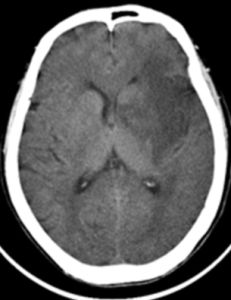

CT表現:硬腦膜外血腫絕大多數(85%)都有典型的CT特點:在顱骨內板下方有雙凸形或 硬膜外血腫梭形邊緣清楚的高密度影,CT值40HU-100HU;有的血腫內可見小的圓形或不規則形的低密度區,認為是外傷時間太短仍有新鮮出血(較凝血塊的密度低),並與血塊退縮時溢出的血清混合所致;少數血腫可呈半月形或新月形;個別血腫可通過分離的骨折縫隙滲到顱外軟組織下;骨窗位常可顯示骨折。此外,血腫可見占位效應,中線結構移位,病變側腦室受壓,變形和移位。靜脈源形硬膜外血腫因靜脈壓力低,血腫形成晚,CT掃描時血腫可能溶解,表現為略高密度或低密度區。少數病人受傷時無症狀,以後發生慢性硬膜外血腫,這時作增強後掃描可顯示血腫內緣的包膜增強,有助於等密度硬膜外血腫的診斷。